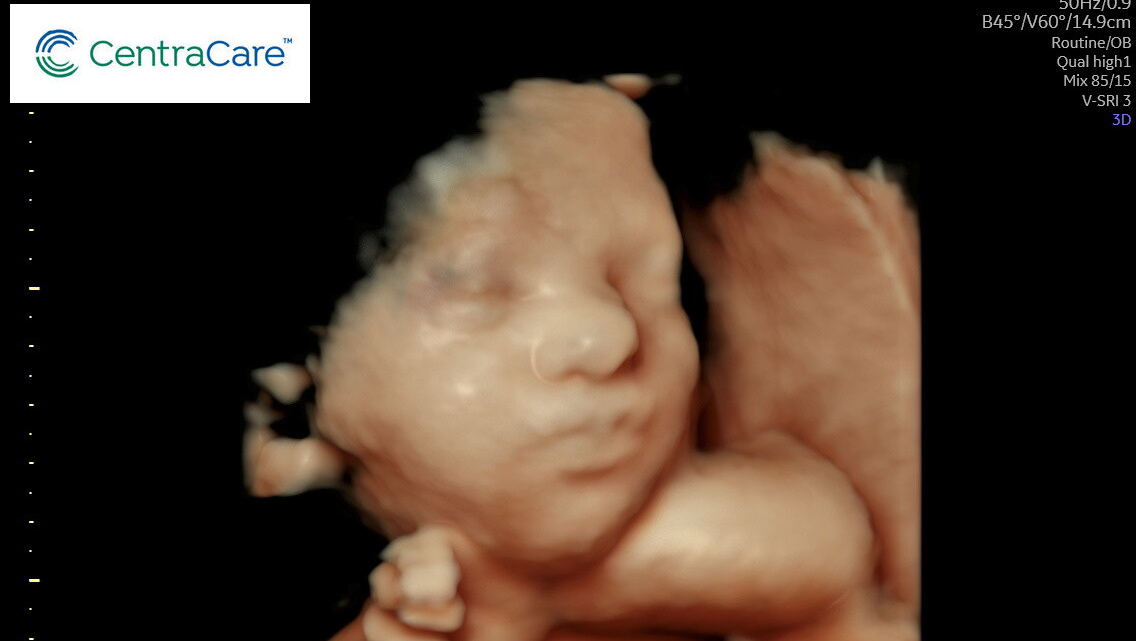

Shantell and Jared are expecting baby #2 on February 5th! Shantell is currently 31 weeks pregnant with a baby girl, and they have recently received some news regarding the baby’s health. From Shantell:

Baby girl is very active and always staying busy! She is measuring about a week ahead. We found out that she has a double bubble (duodenal atresia), where she is unable to digest anything and part of her intestines are completely blocked. Due to this, we will be going to Children’s Hospital in Minneapolis weekly for checkups and plan to have her there. Once she is born, she will have surgery to correct this within the first 3 days of life. We are expecting to be in the NICU for 4-6 weeks while she is healing and learning how to properly digest. This is going to be a rough road ahead of us. We would appreciate extra prayers and support during this time!! ”